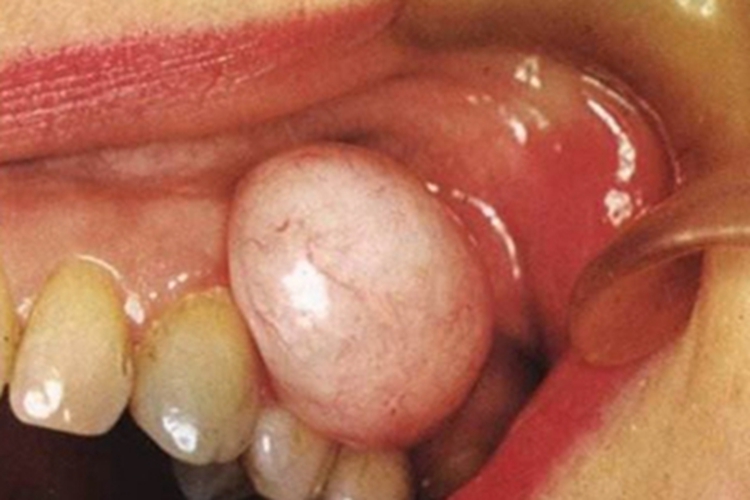

牙龈瘤可表现为牙龈上长出一个大包,如鹌鹑蛋大小,表面光亮,呈粉白色,并有血丝分布,持续发展可使邻近的牙齿移位、松动,甚至导致牙齿脱失。